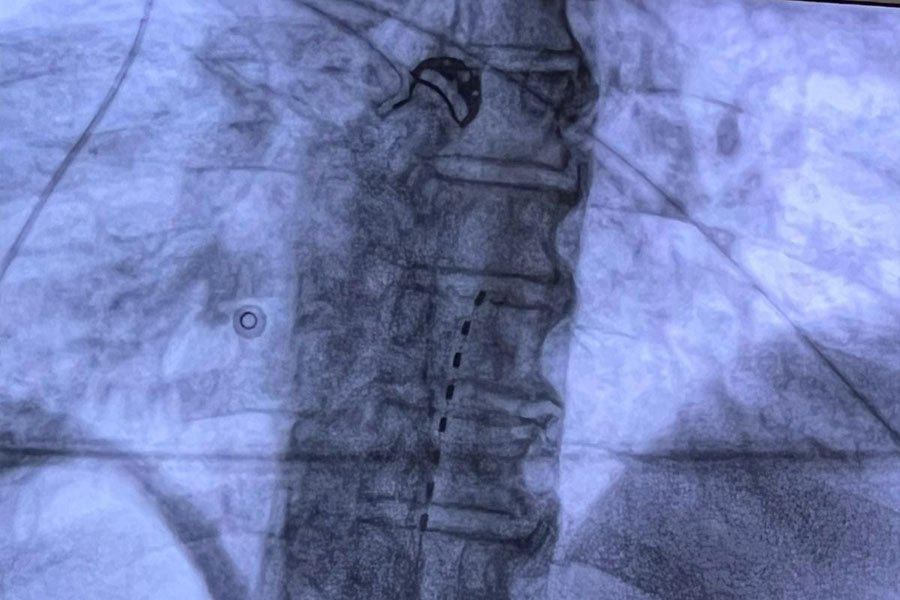

Gli elettrodi vengono posizionati a livello dello spazio epidurale attraverso un’incisione percutanea in anestesia locale, quindi, collegati al generatore di impulsi che viene posizionato dentro una tasca sottocutanea in regione sovraglutea.

• Una prima fase “trial” che consiste nell’impianto del solo elettrodo midollare per testarne la sua efficacia nel controllo del dolore.